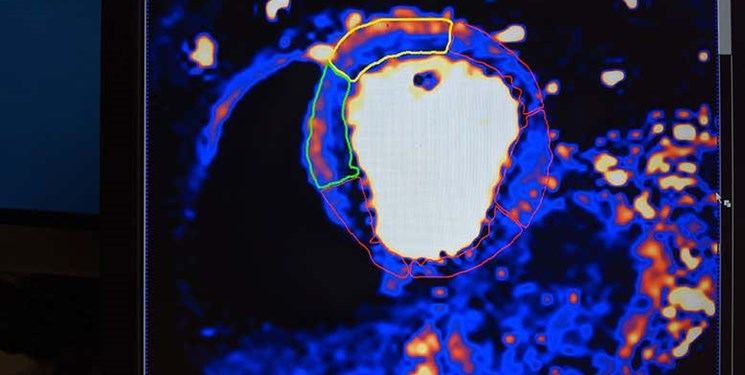

امکان پیش بینی خطر ابتلای کرونایی ها به بیماری های قلبی با هوش مصنوعی

محققان از ابداع یک سیستم هوش مصنوعی خبر داده اند که می تواند پیش بینی کند کدامیک از بیماران کرونایی بیش از سایرین با خطر حمله قلبی مواجه هستند.

پژوهشگران می‌گویند سیستم هوش مصنوعی جدید ابداع شده برای بیماران کرونایی ۲۴ ساعت زودتر احتمال وقوع حمله قلبی در این افراد را اطلاع می‌دهد.

سیستم یادشده که در آمریکا ابداع شده از الگوریتم های جدید هوش مصنوعی بهره می گیرد و برای پیش بینی سکته قلبی، ناهنجاری ضربان قلب، حملات قلبی و غیره قابل استفاده است. طراحی این سیستم با بهره گیری از یک بودجه ۱۹۵ هزار دلاری صورت گرفته است.

با توجه به اثرات منفی ابتلا به بیماری کرونا بر روی سیستم قلبی و عروقی بدن، شناسایی سریع خطراتی که این افراد را تهدید می کند، ضرورتی انکارناپذیر دارد. طراحی این سیستم با جمع آوری اطلاعات بیش از ۳۰۰ بیمار کرونایی صورت گرفته است که داده های مربوط به آنها در دانشگاه جان هاپکینز ثبت شده است.